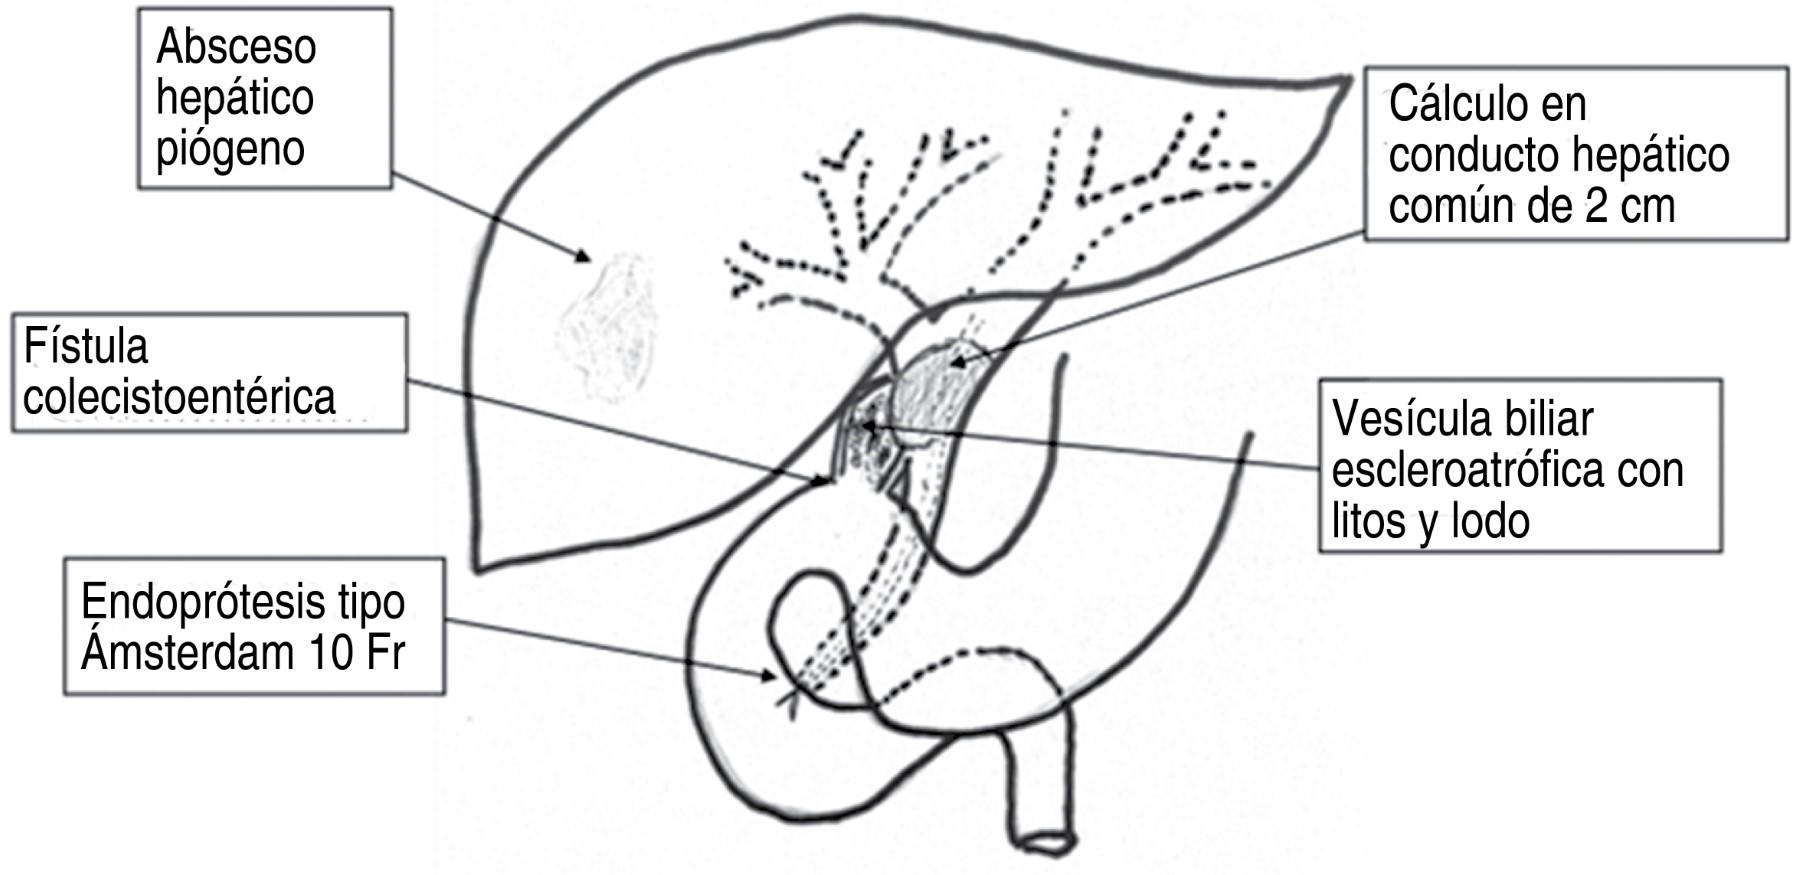

Se le realiza TC abdominal el 02-10-19 que reporta hallazgos de imagen hipodensa de 80 × 53 mm con 23 UH en el segmento VI y VII, en relación con absceso hepático del lado derecho, hepatomegalia a expensas del mismo lóbulo, presencia de neumobilia, la cual aparentemente se observa en comunicación con la pared anterior de la vesícula biliar, escaso líquido libre en hueco pélvico, derrame pleural bilateral y atelectasias pasivas. De igual forma se solicita CPRE el 09-10-19 que reporta colédoco de 6-7 mm, conducto biliar común de 10 mm, se observa defecto de llenado circular de aproximadamente 20 mm que retrasa el vaciamiento del medio de contraste de la vía biliar reportando probable síndrome de Mirizzi tipo IV y fístula bilioentérica de sitio a determinar. Se realiza esfinterotomía, barrido con cánula litotriptora y colocación de endoprótesis tipo Ámsterdam de 10 × 10 cm (Figura 2).

Se realizó incisión subcostal derecha con hallazgos de fístulas colecistobiliar al hepático común, y colecistoduodenal a la primera porción (Figura 4).

Al disecar el plastrón se abre la vesícula biliar escleroatrófica sobre el lito palpado, extrayéndose la prótesis de Ámsterdam del interior de vía biliar principal, junto con lito de 2 cm enclavado en hepático común, resultando un defecto de 2 cm que involucra el hepático común y parcialmente el conducto hepático izquierdo, así como un orificio fistuloso de 3 mm del remanente vesicular a la rodilla duodenal, se decide cierre de fístula colecistoduodenal con una jareta de polipropileno 2-0 y con tres puntos separados de polipropileno encima de la jareta, derivación biliodigestiva de carácter curativa del yeyuno al hepático común en una sola boca con el hepático izquierdo (técnica de Hepp) en "palo de golf" con puntos separados y 10 ml de sellador de fibrina alrededor de la anastomosis, finalizando la Y de Roux yeyuno-yeyunal a 40 cm de la derivación biliodigestiva en forma transmesocólica, fijando el asa yeyunal al mesocolon con puntos separados de polipropileno 3-0 (Figura 5).